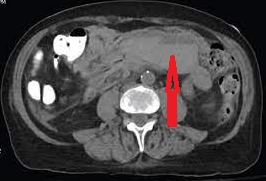

Very large incisional hernia. Red arrows - Separated abdominal walls - atrophic rectus abdominis muscle (Courtesy Dr. V. Penopoulos)